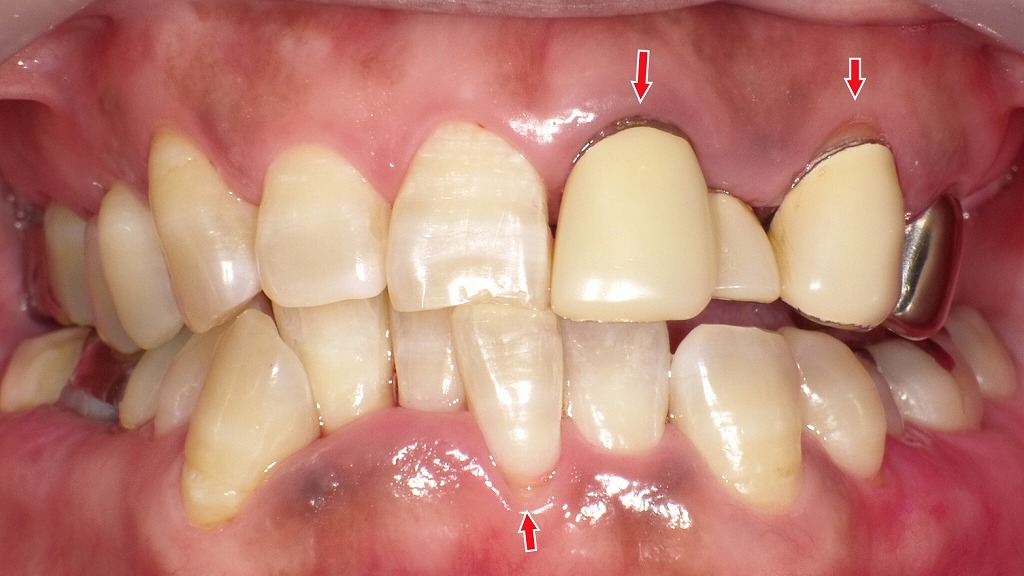

正しい歯磨きでここまで変わる:歯周病改善のビフォー&アフター

赤く腫れた歯ぐきと、クラウン周囲や前歯に付着したプラーク・歯石が見られ、歯周病が進行した状態です。

歯ぐきが腫れて盛り上がることで、歯と歯の境目が不明瞭になり、清掃が難しく悪循環に陥っていました。

丁寧なブラッシングとクリニックでのクリーニングにより、歯ぐきの腫れが軽減。

腫れが引いたことで歯ぐきが“下がったように見える”部分がありますが、これは歯周病が改善したサインです。

歯と歯ぐきの境目が明確になり、毎日の清掃がしやすい状態になりました。